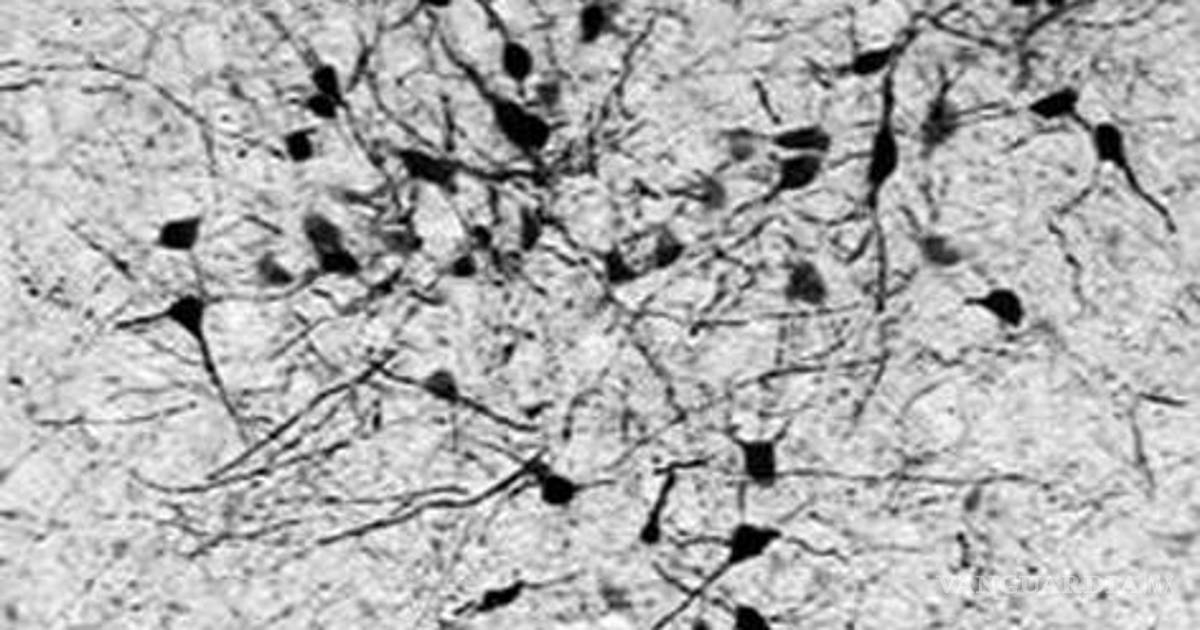

Científicos del Karolinska Institutet, dependencia que otorga los Premios Nobel de ciencia, han identificado un nuevo grupo de células nerviosas en el cerebro, las cuales son responsables de regular las funciones cardiovasculares, lo que podría dar nuevas herramientas para tratar este tipo de enfermedades.

El estudio, elaborado con ratones, permitió detectar este tipo de neuronas que se desarrollan gracias a la intervención de la hormona tiroidea, la cual se expresa en las glándula tiroides, de acuerdo a un comunicado del instituto.